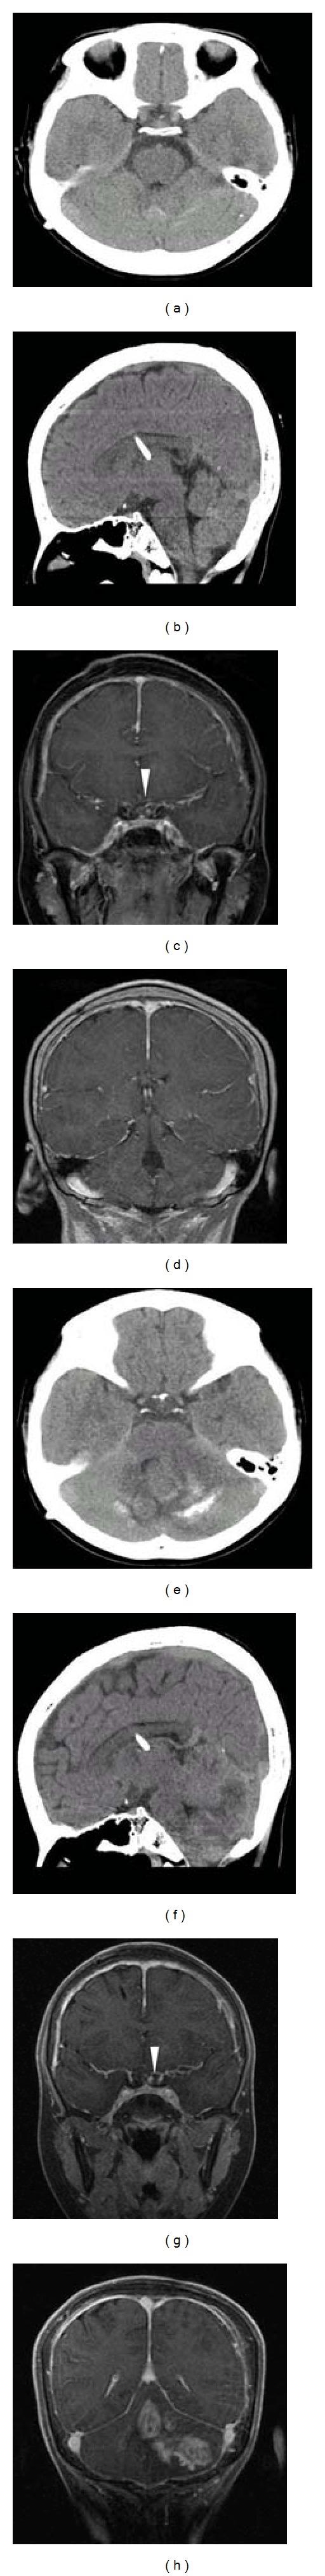

Secondary glioblastoma multiforme (sGBM) can occur after a long latency period following radiation treatment of various diseases including brain tumors, leukemia, and more benign disorders like tinea capitis. Outcomes of radiation-induced sGBM remain poor in both children and adults. We report a case of a 16-year-old girl with a history of disseminated juvenile pilocytic astrocytoma treated with chemotherapy and craniospinal radiation 9 years prior who developed sGBM in the absence of a tumor predisposition syndrome. She presented with a several-week history of headaches and no acute findings on computed tomography compared to baseline neuroimaging 3 months prior. Repeat computed tomography performed just 3 weeks later for worsening headaches revealed a new large posterior fossa tumor where pathology confirmed the diagnosis of sGBM. In spite of maximal surgical resection, reirradiation, and adjuvant chemotherapy, she died 1 year postdiagnosis. Our case highlights the potential late effects of high-dose cranial radiation, how symptomatology may precede neuroimaging findings, and the rapid formation of sGBM that mirrors that of de novo Glioblastoma Multiforme.